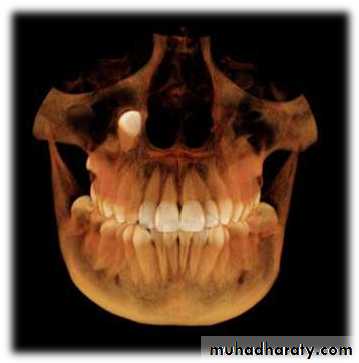

A study was done by Ali Alqerban et al AJODO March

2015, to compare 3D CBCT images of unilaterally

impacted canines with the normal contralateral sides,

and to detect possible radiographic factors involved in

maxillary canine impaction.

Prediction of the probability of canine impaction based

on CBCT was excellent. The canine angulation to the

lateral incisor on the coronal view, the canine cusp tip to

the occlusal plane on the sagittal view, and the canine

crown position were the strongest predictors based on

the CBCT radiographs and may help orthodontists to

identify the probability of impaction for optimally timing

the intervention.

Cone-beam computed tomographyand the orthosurgical management of impacted

teethCBCT imaging can be used to interpret buccolingual

information in detail, to distinguish and define the extent and

depth of root resorption, and to delineate long-axis orientation

of unerupted teeth, including root apex location. It is able to

synthesize traditional panoramic and cephalometric

radiographs. permits oral surgeons to visualize the position

and surgical anatomy of the tooth as it will be seen in the

operating theater and allows orthodontists to plan directional

traction.